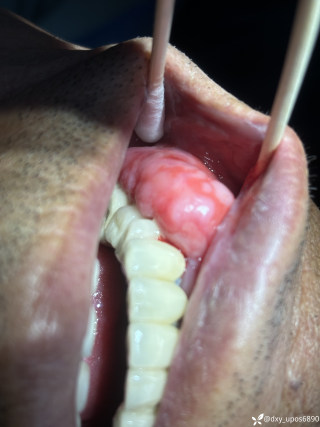

第一次听护士教育病人,你这纹身关键时刻会要你的命!

病例信息【患者信息】:男、16岁【主诉】:全身皮肤瘙痒伴皮疹10分钟【现病史及既往史】:10分钟前患者骑摩托车行驶途中,突感全身瘙痒,奇痒无比伴全身发热,心跳加快。急诊就诊,既往无类似病史,否认咽喉梗阻感、胸闷、气短、呼吸困难、恶心、呕吐、腹泻、乏力等不适。【检查】:血压:138/80mmHg,心率:116次/分,呼吸:21次/分。【临床诊断】:急性荨麻疹【治疗经过及结果】:给予吸氧、肌注扑尔敏1支,口服氯雷他定1片,静滴甲泼尼龙40mg后瘙痒明显减退,皮疹消失。病例讨论双手十指及双足未纹身,护士最后穿刺左手大拇指。